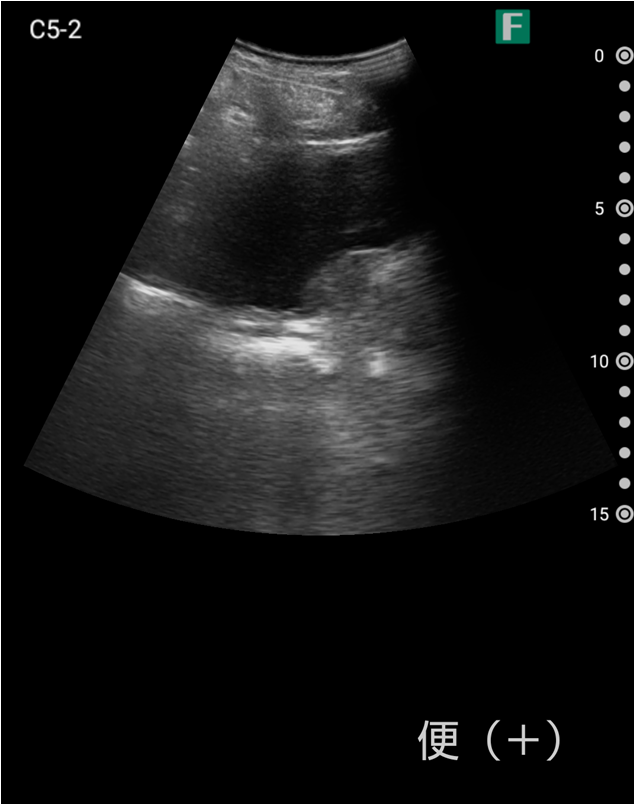

もう一つは入院患者様に対しての具体的な使用事例を紹介します。朝の回診の際にiViz airを使用し、例えば腹水のある患者様を診た際は、「今日は水の量が少なく、そこまでお腹は張ってないですね」、「今日はここに水が溜まっているんですけど、昨日より少ないですよ」など、日々の状態を患者様ご本人に伝えるようにしています。スマホで実際の画像も簡単にお見せできるので、患者様に実際に見ていただくことで少しでも不安を和らげてもらえるように心がけています。

そうして積極的に話をすると、不安そうな表情をする患者様はあまりいらっしゃらない印象を受けています。iViz airがあると患者様と会話をするきっかけにもなるため、コミュニケーションツールとしても実用的だと感じた事例でした。